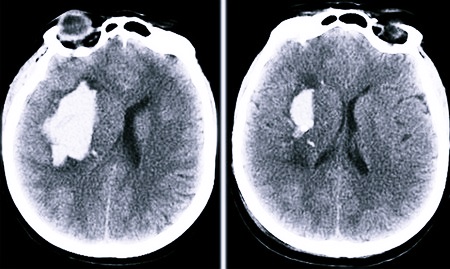

Если кровоизлияние достаточно обширное (более 30 куб. см.) и располагается в глубине ткани мозга, то есть вероятность прорыва крови в жизненно важные мозговые структуры. Подобный процесс зачастую приводит к летальному исходу. Основная симптоматика в этот момент: серьезное ухудшение состояния, потеря сознания, псевдосудорожные признаки, нарушение важнейших функций (сердца, дыхательной системы).

- При высоком артериальном давлении происходит разрыв сосуда с истонченными стенками (из-за развития какого-то заболевания). В результате этого кровь начинает проникать в соседние ткани, что приводит к возникновению гематомы внутри мозга. Формирование гематомы происходит мгновенно. При этой разновидности геморрагического инсульта кровь зачастую прорывается в мозговые желудочки либо субарахноидальное пространство. Из-за чего нарушается венозный отток, начинает формироваться отек, повышается внутричерепное давление. При развитии данных процессов мозг может сместиться, могут быть сдавлены важнейшие структуры, которые регулируют работу дыхательных органов и сердца. Именно поэтому геморрагический инсульт является столь тяжелым заболеванием, которое отмечается низкой выживаемостью.

- Компьютерная томография.